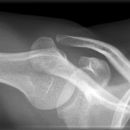

Schulter seitlich (Y-View)

Bei Luxation zusätzlich zur glenoidtangentialen Aufnahme problemlos durchführbar! Axiale Aufnahme schmerzbedingt meist nicht möglich.

- Skapula bildet sich als Y ab

- Humeruskopf projiziert sich in das Glenoid? Luxation? Luxationsrichtung?

- Weite des subacromialen Raumes exakt nur in der 10 – 15° nach kaudal angulierten Aufnahme bestimmbar („Morrison, Outlet View“)! Normalerweise 1 - 1,5 cm, < 6 mm -> wohl pathologisch, Impingment wahrscheinlich

- Normvarianten: Os glenoidale (akzessorischer Ossikel kaudal des Glenoids), persistierende Akromion- oder Korakoidapophyse, entwicklungsbedingte Pfannenranddefekte

- Schulterluxationen:

- Anteriore Luxation (2) 95%= anteriore infraglenoidale Luxation, Kopf liegt vor Glenoid

- Posteriore Luxation (2) 3%: wird häufig übersehen! Kopf liegt hinter Glenoid, Hochstand des Humeruskopfes, fixierte Innenrotation des Humeruskopfes => atypische Projektion des Humeruskopfes: “ drumstick or bulb appearance“ (Birnenform), Muldenzeichen („trough line“), „rim sign“ in der ap bzw. glenoidtagentialen Aufnahme.

Zweite Ebene, z.B. transskapuläre Aufnahme zeigt die Richtung der Luxation. Cave. rein klinische Diagnose!

- Begleitverletzungen? (-> heute umfassend mit CT/MRT zu beurteilen)

- Tuberculum majus (15%)

- Pfannenrand

- Hill- Sachs Läsion = Dorsokraniale Humeruskopf-Impressionsfraktur (50%) (Aufnahme der 1. Wahl: Stryker oder CT)

- umgekehrte Hill-Sachs Läsion = anteromediale Impression nach hinterer Luxation

- Bankart-Läsion: Abriss des vorderen Labrum-Kapsel-Komplexes bzw. Abrissfraktur des vorderen unteren Glenoidrandes (-> CT-Athrographie, Arthro-MRT)